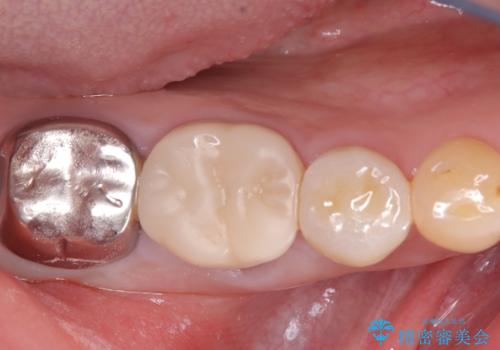

【セラミッククラウン】銀歯を白くしたい

- 主訴:笑った時に下の銀歯が目立つので、白いものに替えたい

失活歯に保険適応のメタルクラウンがセットされていました。

根尖病巣と根管内に破折ファイルを認め、ファイル除去は困難だということをお伝えし、根管治療・土台・クラウンのやり替えとなりました。